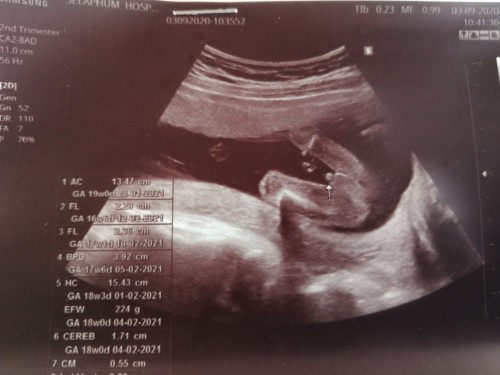

ชัดเจนเหมือนกันเลยครับ อันนี้ตรวจตอน 19วีค ทัอง2ค่ะ ท้องแรก เด็กหญิง😂

สอบถามค่ะ แบบนี้ชายหรือหญิงค่ะ สอบถามผู้รู้ค่ะ

ชัดขนาดนี้ก็คงจะผู้ชายแหละค่ะ 😂

ชัดขนาดนี้ก็ต้องผู้ชายแล้วคะ🤣

ชายแท้ด้วยตาเปล่าเลยค่ะ🤣🤣🤣🤣

ผู้ชายเลยคะ น้องเห็นชัดมากคะ

ชายคะแม่ มาเป็นลำเลยนะลูก5555

ชัดมากเลยคร้าแม่ ผู้ชาย